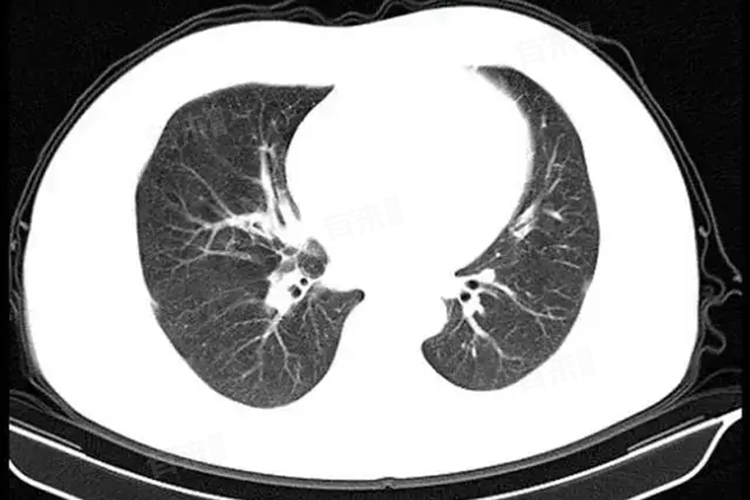

- 肺部CT是一种影像学检查方法,通过使用X射线和计算机技术,能够生成高分辨率的肺部图像。这些图像不仅展示了肺部的结构、形态和病变情况,同时也能够显示肋骨的形态和位置。在肺部CT检查中,如果肋骨存在明显的形态改变或位置异常,如肋骨骨折后的错位、肋骨肿瘤的占位等,这些异常是可以在图像上被观察到的。

- 虽然肺部CT可以显示肋骨的形态和位置,但对于肋骨骨折的诊断,尤其是隐匿性骨折或轻微骨折,其诊断价值相对有限。因为CT主要是环形平扫,有可能骨折平面扫不到或者漏诊。此时,肋骨的三维CT可能更为准确,能够将肋骨进行360°重建,从而发现隐匿的骨折并排除多根多段的肋骨骨折。